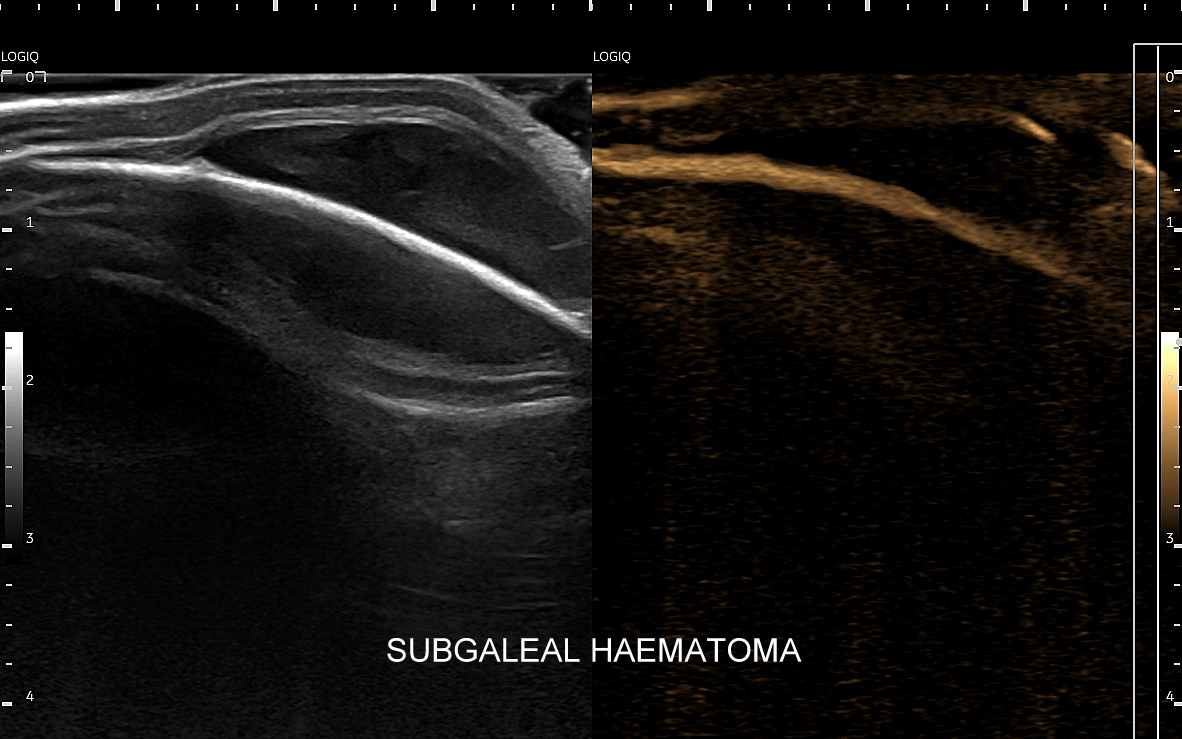

W obrębie powłok czaszki spotkać można również takie patologie jak naczyniaki, tłuszczaki, torbiele, czy potencjalnie niebezpeczne krwiaki podczepcowe.

Poza strukturami wewnątrzczaszkowymi w badaniu USG główki niemowlaka oceniana jest pokrywa czaszki, w tym szwy i kości czaszkowe, tkanka podskórna oraz skóra głowy. Badanie USG szwów czaszkowych ma istotne znaczenie przy ocenie niesymetrycznego lub zdeformowanego kształtu głowy w kontekście rozpoznania kraniosynostozy (ang. craniosynostosis), tj. stanu, w którym dochodzi do przedwczesnego oraz nieprawidłowego zarastania szwów. W kraniosynostozie w miejscu zarastania tworzy się zwykle patologiczne twarde uwypuklenie / guz, które posiada charakterystyczny obraz sonograficzny pozwalający na rozróżnienie zarastania szwów w przebiegu kraniosynostozy od przedawkowania witaminy D, czy fizjologicznej wcześniejszej fuzji kości czaszki.